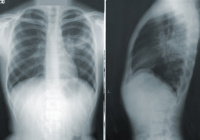

Названы группы россиян, наиболее подверженные пневмонии

Специалисты Роспотребнадзора назвали россиян, наиболее подтвержденных внебольничной пневмонии.